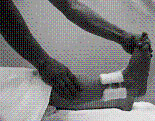

患部の固定、腫脹軽減を目的に脛骨内果部の後方、側方より圧迫枕子を加えた。腓骨は転位がないため前後方向からの圧迫枕子のみとした。両骨とも患部の動揺を防ぐため、テープによる固定を行った。冷湿布を行い、大腿中央より足先にかけて背側にクラーメルシーネをあて、包帯にて固定を行った。固定肢位は膝関節軽度屈曲位、足関節良肢位とした(図3)。右患側肢への体重付加を禁止。松葉杖歩行を指示した。

|

整復後の転位を防ぐため、内果部に綿花枕子をあてる。 |

整復後の転位を防ぐため、外果部に綿花枕子をあてる。 |

テーピによる固定 |

クラーメル、包帯による固定 |